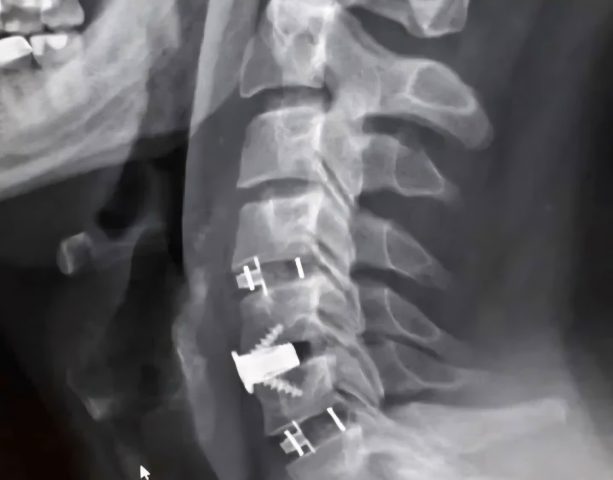

В стационаре ему диагностировали диско-остеофитный стеноз позвоночного канала на уровне нескольких шейных позвонков. Это означает, что произошло сужение канала, а расположенные в нем структуры оказались сдавленными.

Коллектив врачей под руководством заведующего нейрохирургическим отделением Павла Юрова провел операцию, особенность которой состоит в применении комбинированной техники. Воронежцу устранили компрессию и выполнили стабилизацию позвоночника, одновременно усилив его различными титановыми конструкциями.